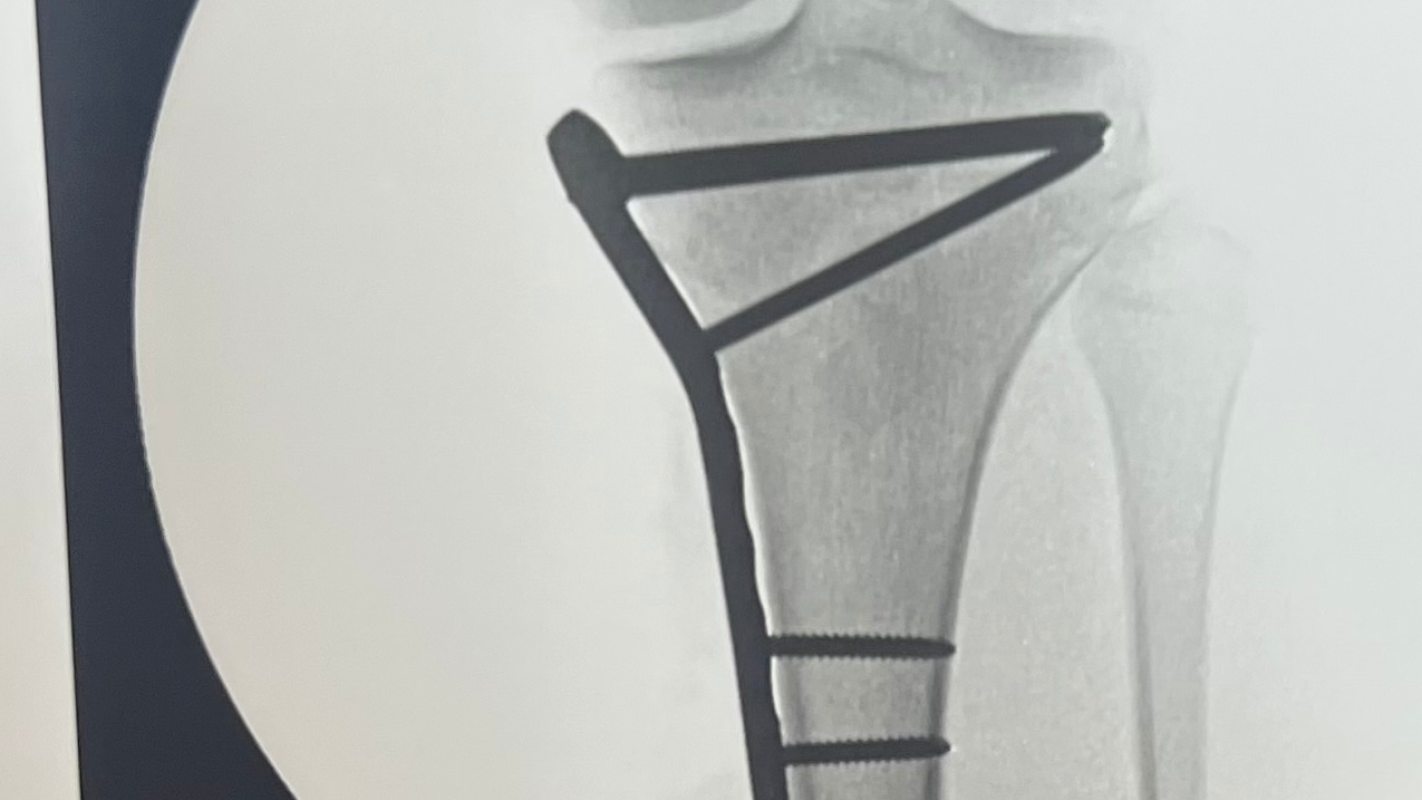

Abushamli’s wife has unfortunately been diagnosed with back problems that need immediate surgery. Her back injury has progressed to the point that Mr. Abushamli’s wife cannot move around much and is in constant pain. On the MRI scan, it was revealed that her back disc was not lined correctly. The doctor requested Mrs. Abushamli to have surgery as soon as the end of April 2024.